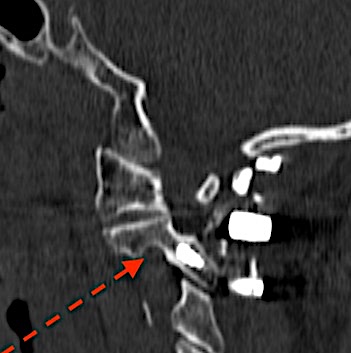

Sin embargo, la reconstrucción coronal del mismo paciente nos indica claramente que la fractura (flecha roja) se ubica en la base de la odontoides